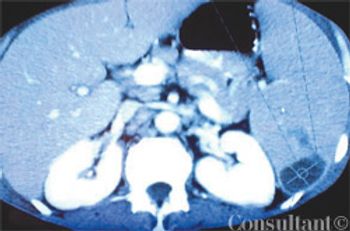

A 51-year-old man with a history of AIDS (CD4 count of 59 cells/µL), anemia, neutropenia, and AIDS-related dementia presented with persistent fever, abdominal pain, and diarrhea of 2 months' duration. He did not adhere to his regimen of HAART and prophylactic therapy with atovaquone and azithromycin.